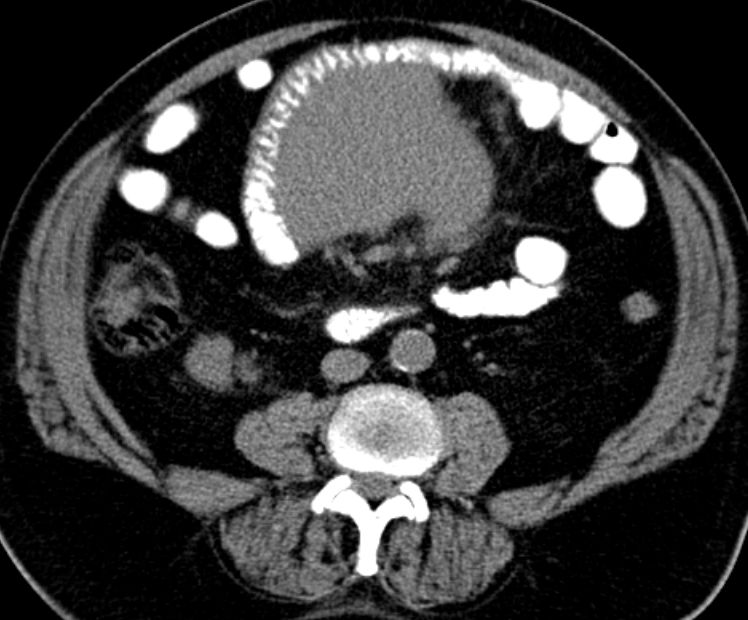

Mesenterialer Bulk |

77-jähriger Mann mit einem abdominalen Tumor und Stenosesymptomatik. Im Dünndarmresektat mit Mesenterialwurzel ein follikuläres Lymphom Grad II-IIIa, FLIPI-Score 2.![]() |

![]() |

![]() | |